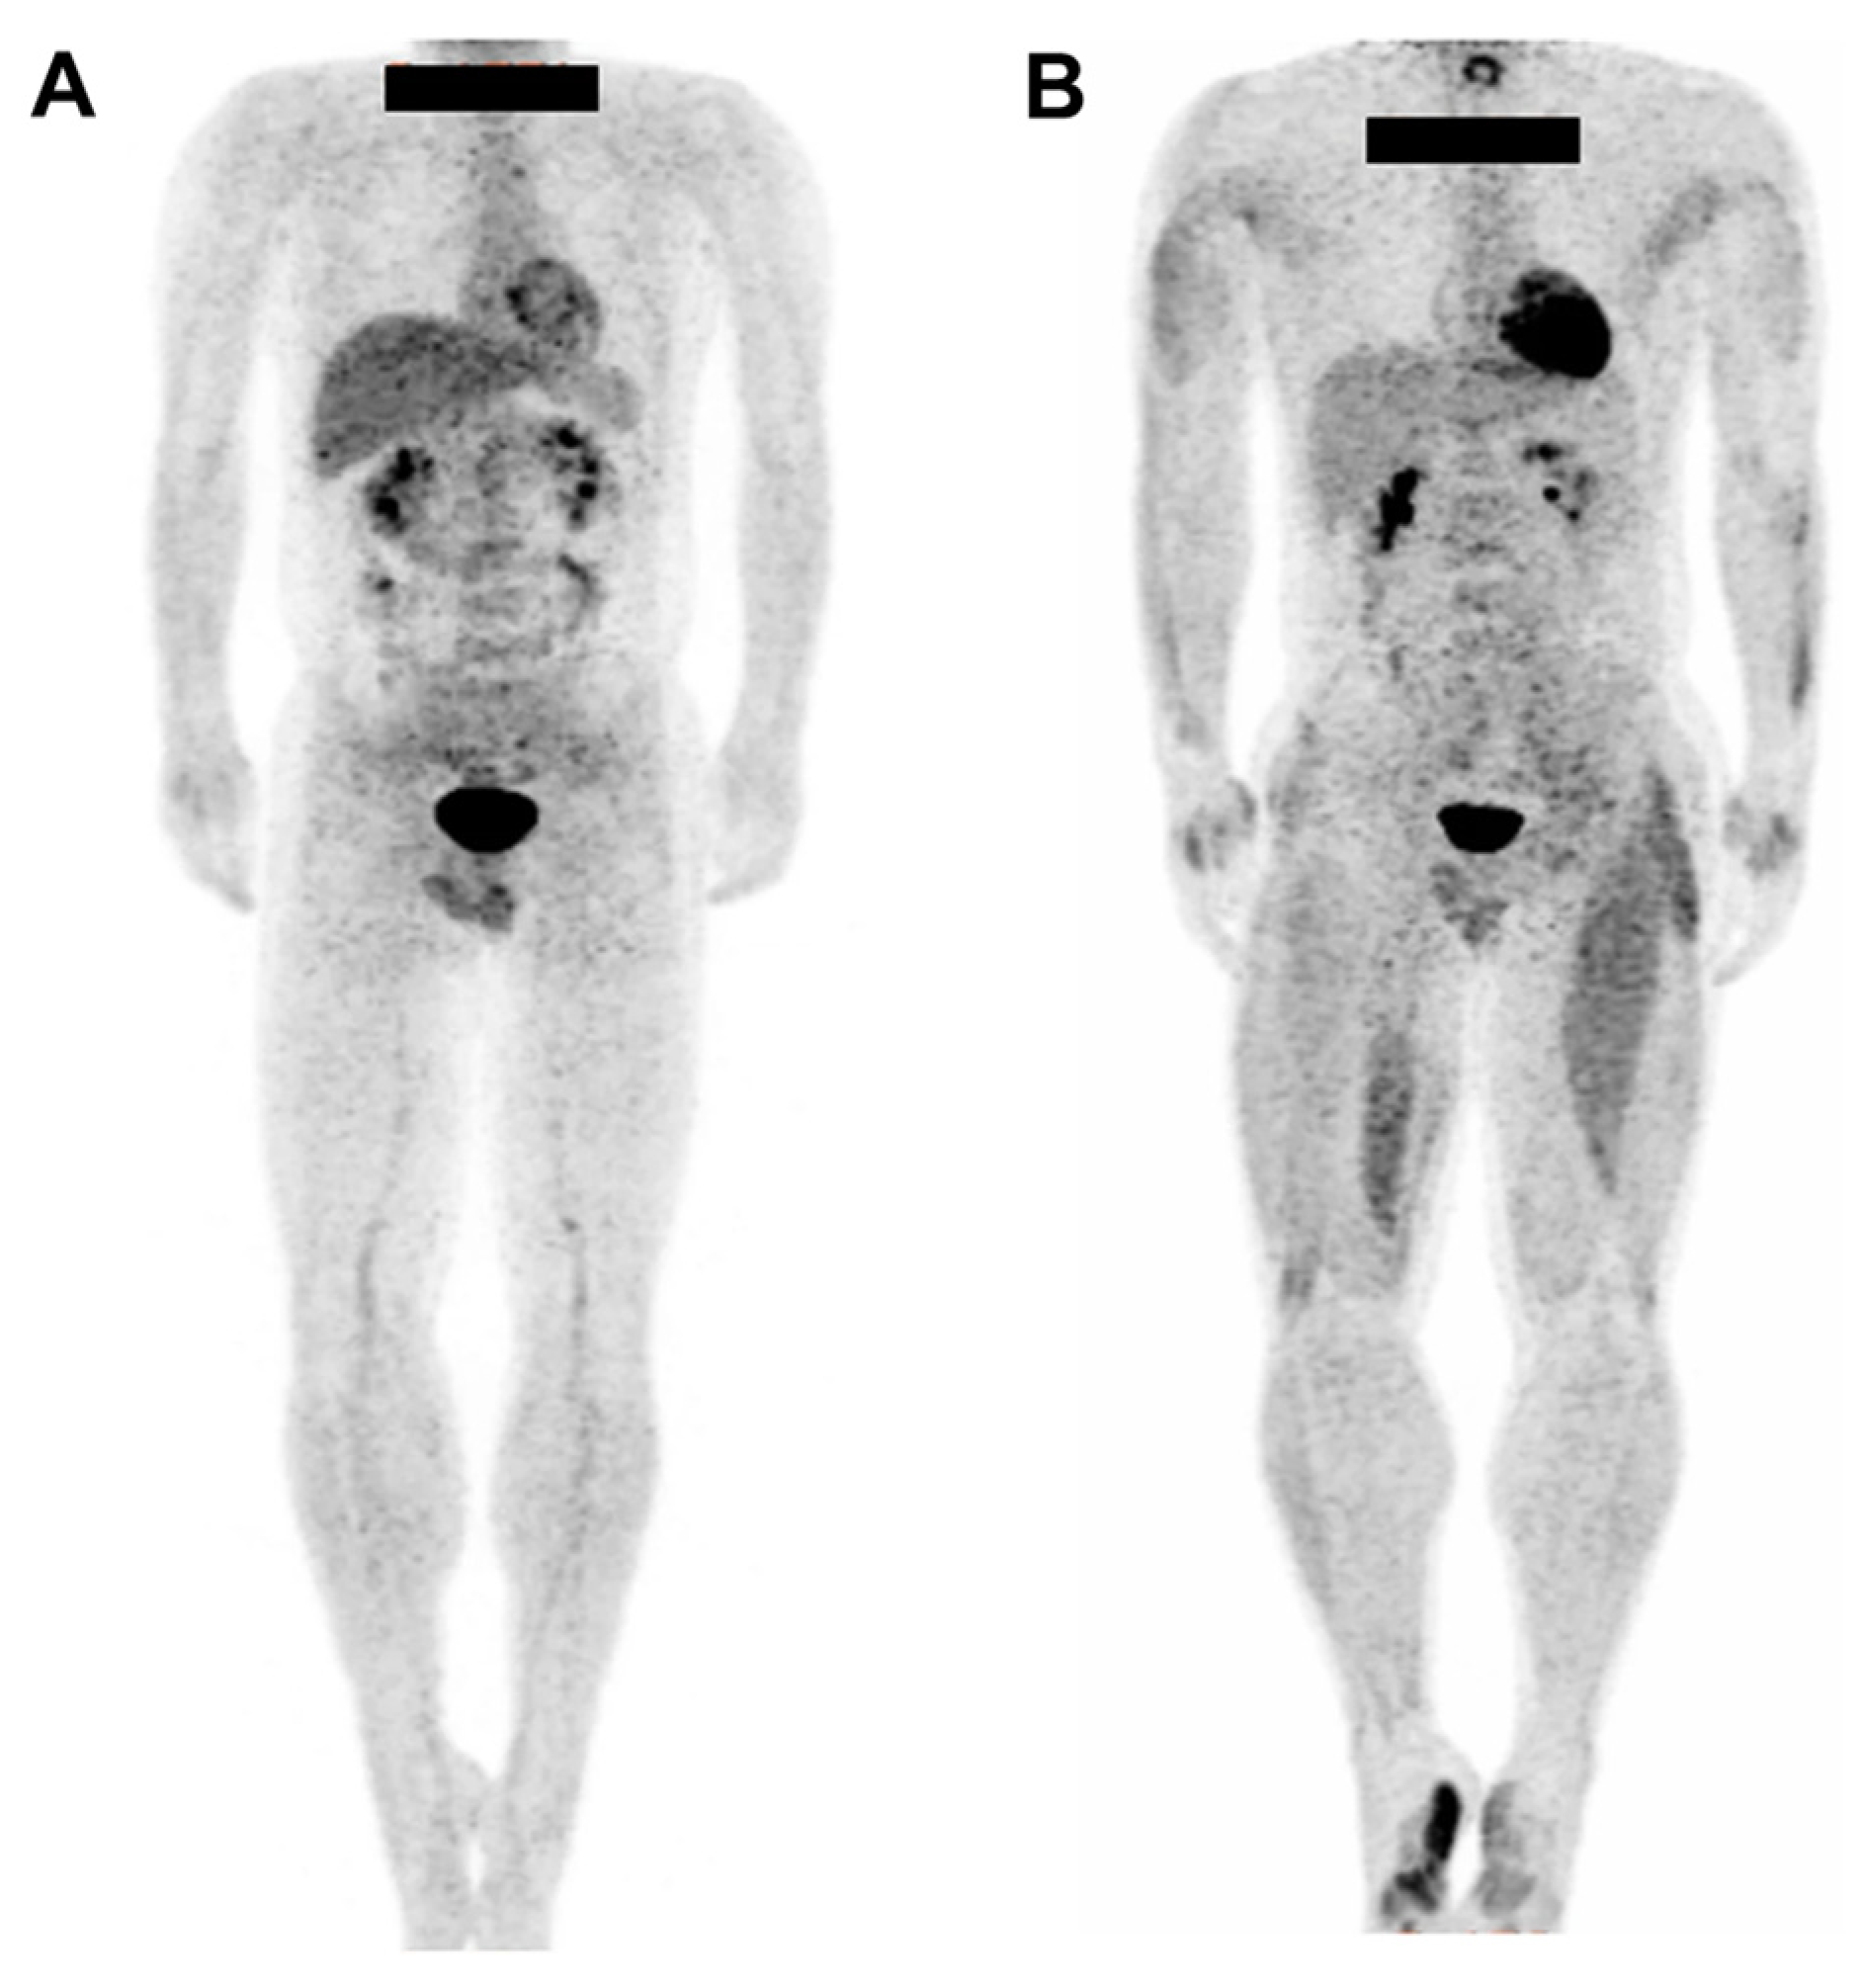

| Healthy volunteers (n = 8) | [18F]FDG was injected during exercise, followed by a whole-body PET scan conducted after the exercise. | [18F]FDG uptake did not increase in the upper body; however, increased uptake was observed in the lower body muscles, including the knee flexors and extraterrestrial and abdominal muscles. | [29] | |

| Healthy volunteers (n = 20) | [18F]FDG was injected 10 min after the start of exercise or after 20 min of rest. Whole-body PET scan was conducted after the exercise or rest periods. | The exercise group exhibited significantly greater uptake than that of the control group in the iliacus muscle and muscles of the anterior part of the thigh. | [30] | |